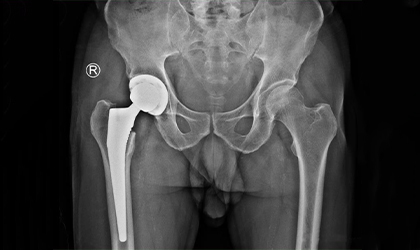

Performing over 500 hip surgeries, Dr. Bipin Theruvil demonstrates extensive expertise in orthopedics. His surgical experience encompasses various procedures such as hip replacement, hip arthroscopy, and fracture repair, ensuring patients receive high-quality care for a range of hip conditions. Dr. Theruvil's proficiency and dedication to advancing surgical techniques contribute to successful outcomes and improved quality of life for his patients.

Explore real-world examples of successful surgical interventions by Dr. Bipin Theruvil. These cases highlight innovative techniques and personalized care that have transformed patients' lives.

Each case study provides detailed insights into the challenges faced, approach taken, and outcomes achieved, demonstrating Dr. Theruvil's expertise in hip and knee replacements.Each case study provides detailed insights into the challenges faced, approach taken, and outcomes achieved, demonstrating Dr. Theruvil's expertise in hip and knee replacements.Each case study provides detailed insights into the challenges faced, approach taken, and outcomes achieved, demonstrating Dr. Theruvil's expertise in hip and knee replacements.